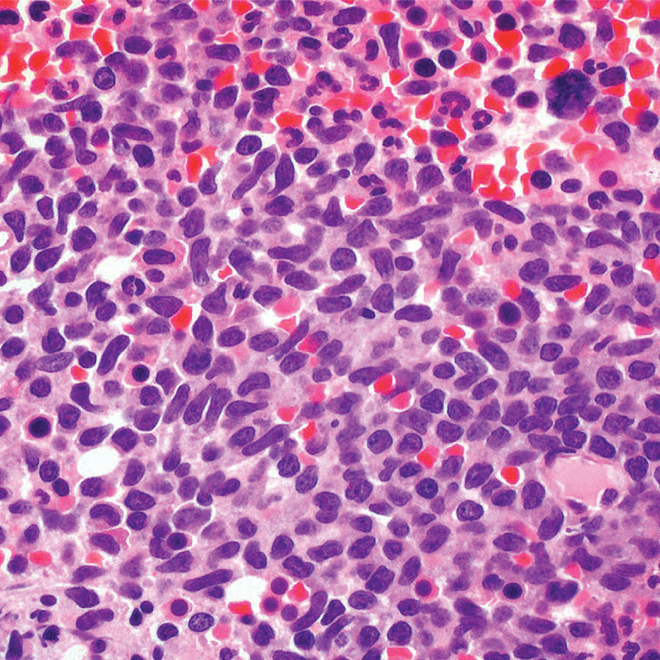

Bone marrow

Core biopsy showing diffuse infiltrate by BPDCN (H&E stain, x600).11

H&E, hematoxylin and eosin.

Main morphologic features of BPDCN biopsy

• Diffuse, monomorphic infiltrate1

• Medium-sized blast cells with irregular nuclei1

• Fine chromatin1

• At least 1 small nucleolus1

• Malignant BPDCN cells do not typically infiltrate the epidermis4